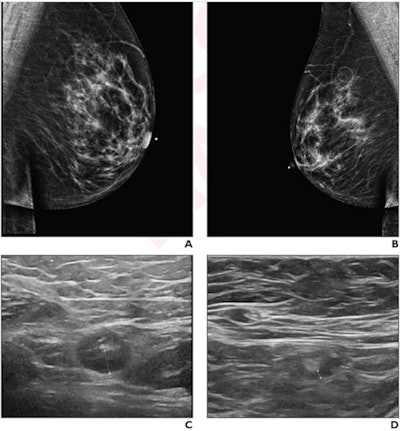

Axillary lymphadenopathy found on breast ultrasound is a known side effect of the COVID-19 vaccine, and although it can cause concern in patients -- whether through symptoms or incidental detection on imaging -- most cases resolve on their own within about three months, the authors noted.

Mema and colleagues explored the time to resolution of vaccine-related axillary lymphadenopathy after a booster dose and evaluated what factors may be associated with resolution times via a study that included 54 patients who presented with unilateral axillary lymphadenopathy after a booster vaccine between 2021 and 2022. The condition was detected on ultrasound exams performed on either an initial breast imaging exam or follow-up prior to screening or diagnostic breast imaging; patients underwent follow-up ultrasound examinations until the lymphadenopathy resolved.

The researchers found that lymphadenopathy resolved at an average of 102 days after the booster dose and 84 days after the initial ultrasound that detected it. They also found that the average time to resolution in the booster dose patients was significantly shorter than the average of 129 days seen in patients after the first dose of the initial vaccine series (p = 0.01), and that age, vaccine booster type, and history of breast cancer were not significantly associated with time to resolution.